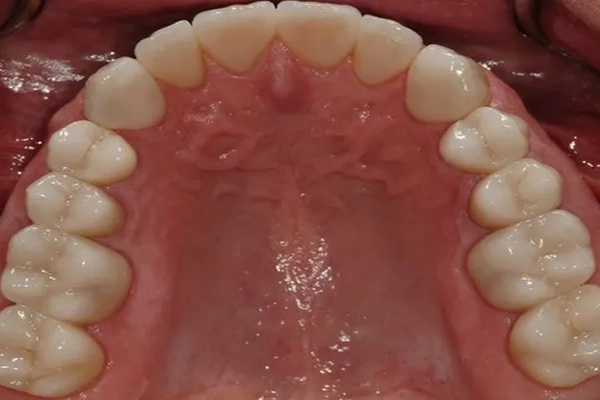

Mercury-Free Dentistry Before and Afters at Suite Dental

After

Before